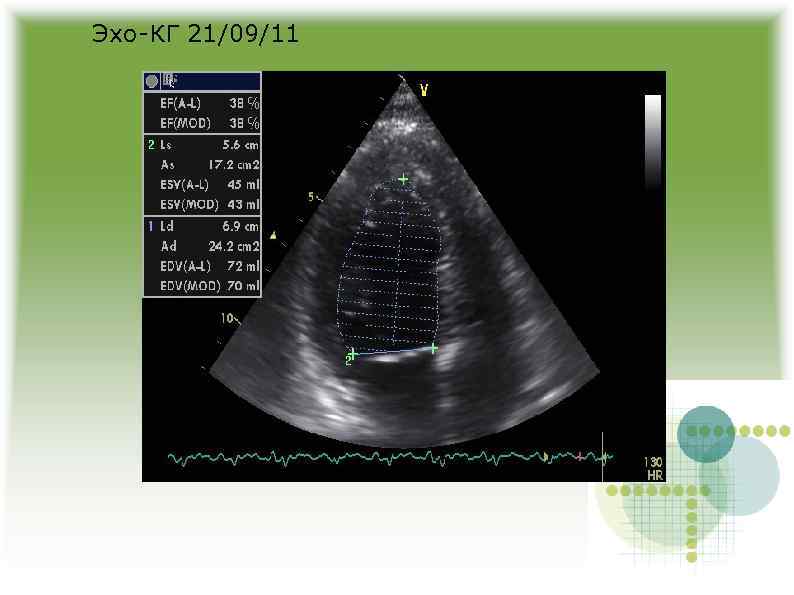

Эхо-КГ 19/09/11 Эхо-КГ 19/09/11

Проводилась оксигенотерапия, назначены диуретики, игибиторы АПФ, бета-блокаторы На фоне лечения – уменьшение одышки, в Проводилась оксигенотерапия, назначены диуретики, игибиторы АПФ, бета-блокаторы На фоне лечения – уменьшение одышки, в легких хрипов нет.